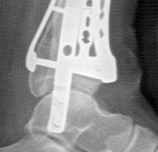

Removal of implants is not mandatory but recommended if implants are prominent under the subcutaneous envelope of the distal tibia. Implant removal should be undertaken only after healing is complete, ie, after 1 year at the earliest. This patient had achieved good radiographic and functional healing at the 1-year postoperative review (Fig 2.2-8 and Fig 2.2-9).

Fig 2.2-8a–b Postoperative x-rays at 1 year showing healed fractures, implants in situ, and limited tibiotalar arthrosis.

1. AP view.

2. Lateral view.